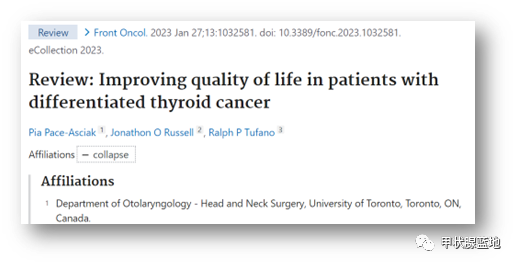

甲状腺是人体中非常重要的内分泌器官,外形像一只美丽的蝴蝶,通过分泌甲状腺激素促进物质和能量的代谢,对人体的多系统具有重要影响。近年来,随着人们体检意识的增强和超声诊疗技术的迅猛发展,甲状腺恶性结节的检出率呈逐年增高的趋势,而一旦确诊,颈部这只美丽的蝴蝶就面临着折翼的风险——外科手术切除。腺体切除、颈前瘢痕、终身服药像一幕幕阴霾,笼罩在患者的头上。 患者小Y是一个23岁年轻美丽的女孩儿,在哈医大一院超声医学科进行超声检查后,发现右侧叶有一枚大小约0.8cmx0.6cmx0.8cm的TI-RADS 4c类结节(图1),并且经过穿刺病理证实为甲状腺乳头状癌。这如同一个晴天霹雳般的坏消息,让这个女孩儿痛苦不已。如果选择手术切除,术后颈部的瘢痕、终身服药的不便、尚未结婚怀孕的现实难题,让小Y难以接受传统手术疗法。在了解到她的困扰后,哈医大一院超声医学科介入团队迅速启动科内会诊及病例讨论机制,在学科主任吴长君教授的提议下,决定采用超声引导下的射频消融治疗,对小Y的恶性结节进行局部灭活,并且尽可能保留正常腺体。通过术前审慎评估,细致准备,消融手术由超声医学科王俊峰副教授主刀。在实时超声的引导下,射频消融针精准的进入恶性病灶内,仅用时3分钟左右,消融范围就完全覆盖病灶(图2)。 治疗过程中,超声介入团队配合默契,采用多种技术保障患者安全,避免了甲状腺周围重要组织(血管、神经)的损伤。治疗取得了圆满成功。术后,小Y开心的笑了,超声介入团队也由衷的为她感到高兴(图3)。 哈医大一院超声医学科主任、博士生导师吴长君教授介绍,超声引导下射频消融治疗甲状腺乳头状癌,具有非常多的优点。在保障治疗效果的同时,可以满足患者个性化的需求。射频消融用时短,术后恢复快,无需终身服药,并且避免了颈部瘢痕,尤其对于爱美女性及拒绝终身服药的患者非常友好,是一种值得大力推广和应用的治疗技术。哈医大一院超声医学科介入团队秉承不断进取、精益求精的理念,着力打造甲状腺疾病诊疗一体化平台,为守护龙江人民的健康不懈努力!